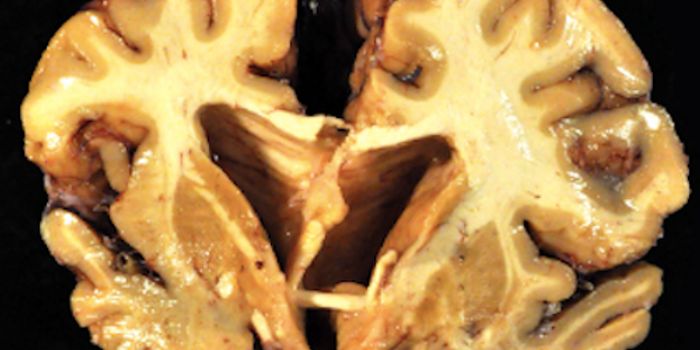

JUL 12, 2018NeuroscienceDementia is a growing problem for healthcare providers, patients, and families. It’s estimated that 47 million peo ...

AUG 02, 2022NeuroscienceRecent allegations of research misconduct have called years of Alzheimer's research into question. The controversy surro ...

OCT 29, 2018NeuroscienceCerebellum play a mjor role in higher -order brain functions beyond the motor specific functioning